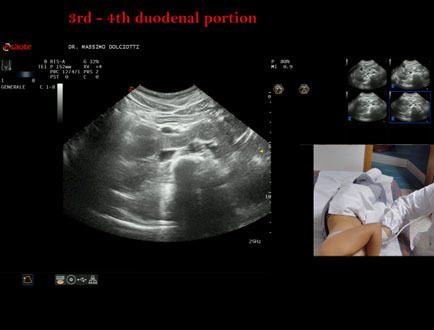

Data inserimento: 19/09/2025

Ecografia del: 10/09/2025

Strumento: Esaote MyLab Eight

Sonda: Convex Multifrequenza 1-8 MHz

Età Paziente: F 24 anni

Motivazione dell'esame:identificazione della terza e quarta porzione duodenale.

Commento all'esame: le immagini ed il video documentano il duodeno ed in particolare la terza e quarta porzione.

Conclusioni: 3° e 4° porzione duodenale (3rd and 4th duodenal portion).

Presentazione: Dr. Massimo Dolciotti - Ancona

Elaborazione digitale: Andrea Dini - Ancona